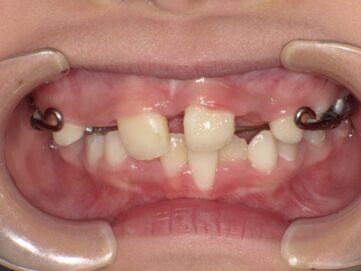

最近では歯並び・噛み合わせが悪い子供が増えてきています。成長期における生活環境や食生活による顎の成長不全が原因だと言われています。噛み合わせが悪いと歯がしっかりと生えることができなかったり、八重歯や出っ歯などの 不正咬合となってしまう可能性があります。

また、その他にも呼吸障害も誘発されたりなど、身体にも影響を及ぼします。これらは、顎骨の未発達が原因で起こる事が多いですが、小児期の矯正治療で治す事が可能です。

顎顔面矯正治療とは、歯並びだけでなく噛み合わせや顎関節を考慮して行う矯正治療のことです。顎顔面矯正治療により、顎関節症の緩和や鼻づまりの改善効果も期待できると言われています。主に、小児期に行い、見た目をよくするだけではなく、顎の骨や顔の骨格を正しい形に導きます。

歯並びの悪い原因としては顎の急な成長によるものが多く、装置で顎を広げる事で歯が綺麗に並ぶスペースを確保します。

青島歯科クリニックでは、顎顔面矯正治療によるお子さまの歯並びを綺麗に整える治療を行っており、お子さまの歯並びを骨格から正しく治し、成長を一緒にサポートさせて頂いております。